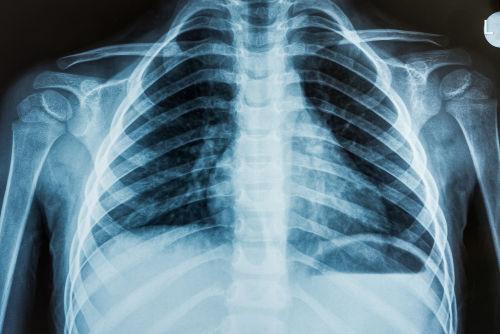

raios –x podem ser usados como meio de diagnóstico e de terapia. Como

meio de diagnóstico, os raos – x podem ser usados na detecção de ossos

partidos, investigação de desordens respiratórias ou digestivas. No caso

Durante o uso dos raios – x na medicina, é muito importante controlar a

dosagem (a frequêcia) que deve ser usada para cada tipo de diagnóstico

ou terapia, porque os raios – x podem causa a destruição de tecidos vivos.

Por isso, não é conveniente que um paciente esteja constantemente

exposto aos raios –x, daí que não seja conveniente fazer duas radiografias

da mesma parte do corpo ( do tórax por exemplo) num intervalo de tempo

inferior a seis meses. Resumindo podemos afirmar que os raio – x têm